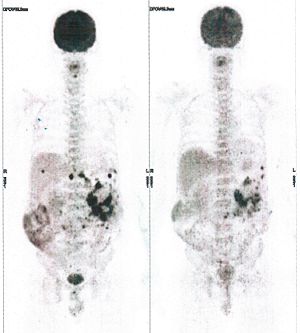

CASE NO: 5 (BREAST CANCER)

A middle-aged woman with breast cancer that has spread to the anterior chest wall, and numerous chemotherapy could not stop the spread of cancer. After a few treatment, almost all the cancer went into remission. About 6 months later, she is still in remission.

CASE NO: 6 (BREAST CANCER)

A middle-aged women treated for breast cancer now presents with massive liver metastases and a few bone metastases. She refused conventional chemotherapy and came to see us. After just 2 treatment, most of the cancer went into remission and those remaining are less active. Treatment will continue until complete remission.

CASE NO: 7 (BREAST CANCER)

A middle-aged woman treated for breast cancer now presents with bone and liver metastases. After a few treatment, most of the cancer went into remission, and the remaining ones are less active.